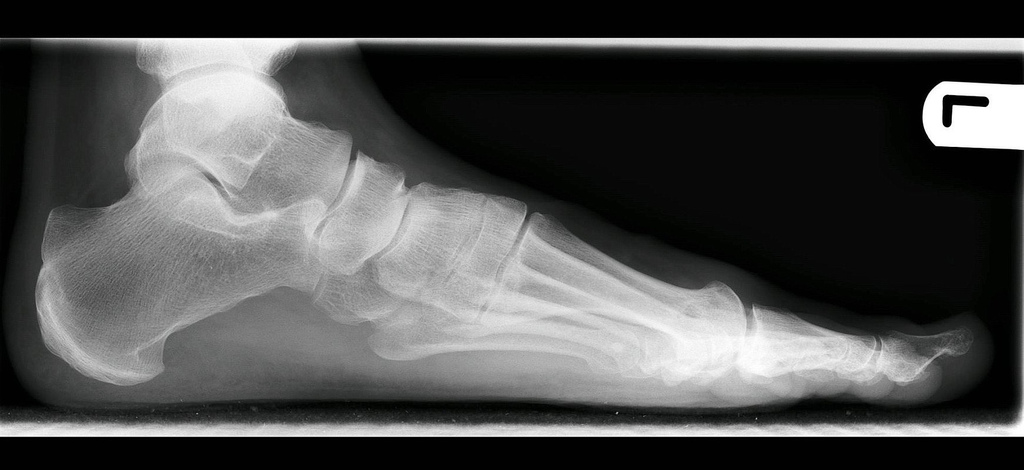

Arthritis

For quick aid from joint pain, have ginger tea. It would bring down inflammation & pain of the joints and offer much aid. It also soothes muscles & treats stiffness.